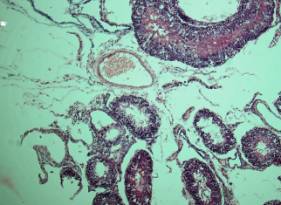

Гистологически в

яичках наблюдались явления субатрофии, которые выражались в фиброзе стенок

сосудов, базальных мембран семенных канальцев, исчезновением сперматоцитов 2-го

порядка (Рис.1); у 38 (16,9%) обнаружен

туберкулезный орхит (Рис.2).

Рис. 1. Б-ной К.,27 лет. Стаж

курения марихуаны 9 лет. Субатрофический орхит.

Липофусциноз.

Окраска гематоксилин – эозин. х 160.